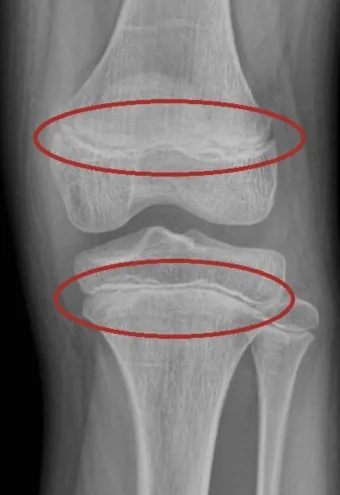

성장판은 하나의 문이 갑자기 '딱' 닫히는 것이 아닙니다. 손가락, 발가락, 손목, 발목, 골반, 척추 순으로 뼈 끝 쪽의 연골이 굳어져 가는 과정은 꽤 오랜 시간이 걸려요. 성장판의 닫히는 시기는 개인차가 매우 크답니다.

일반적으로 여성은 14-15세, 남성은 16-17세에 성장판이 닫히기 시작하지만, 완전히 닫히는 것은 만 19-20세경이에요. 하지만 여기서 중요한 건, 성장판 검사에서 '닫혔다'고 나와도 검사 오차가 있을 수 있고, 미세하게 남아있는 성장판으로 인한 성장 가능성이 남아있다는 점입니다.